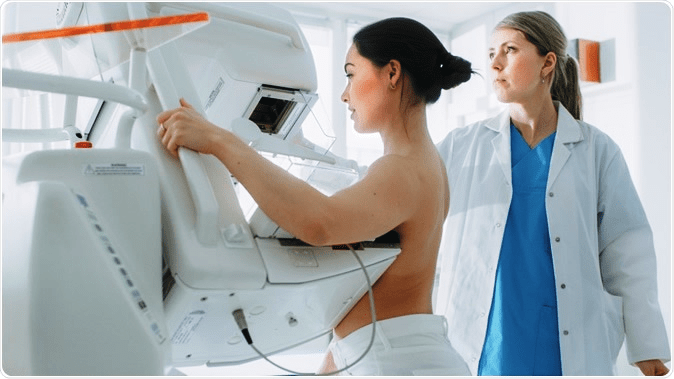

- Mammogram –A mammogram is an X-ray imaging test that examines breast health. It’s the most efficient tool to help detect breast cancer, especially at its earliest stage. And menopausal women, who are in the highest risk category, should absolutely have a mammogram done annually to eliminate the risks. A mammogram can often detect breast cancer even when it’s just starting out or even before a lump can be felt. At this stage the cancer is also the easiest to treat.